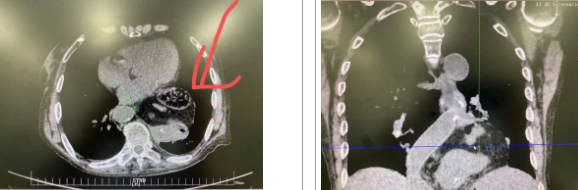

據(jù)了解,患者多年來進食后出現(xiàn)惡心、嘔吐,卻未到醫(yī)院進行檢查。3個月前患者突然出現(xiàn)無尿,全身腫脹等情況才前往就醫(yī),卻遭多家醫(yī)院拒收,輾轉(zhuǎn)來到我院就診。檢查發(fā)現(xiàn)患者已患宮頸癌、進而引起腎后性腎衰、同時合并膈疝、出現(xiàn)泌尿道感染,病情及其復(fù)雜。

經(jīng)泌尿外科積極救治,患者腎衰癥狀緩解,隨后轉(zhuǎn)入放射治療中心進行宮頸癌根治性放療。放療期間,患者惡心、嘔吐癥狀逐漸加重,后期無法進食,排除機械性腸梗阻和放療因素,考慮因長期膈疝加重引起,經(jīng)胸外科會診后轉(zhuǎn)入胸外科一病區(qū)準備手術(shù)治療。

麻醉手術(shù)中心副主任丁倩為減輕患者術(shù)后不適,實施單腔聯(lián)合支氣管封堵插管,同時進行了肋間神經(jīng)阻滯麻醉。術(shù)中發(fā)現(xiàn)患者膈疝巨大,食管和疝囊分界不清,部分胃組織和結(jié)腸疝已進入胸腔。李文海憑借豐富的臨床經(jīng)驗,仔細辨別解剖變異,有序完成分離、縫合、修補等一系列操作,胸外科穆強副主任醫(yī)師、劉歡住院醫(yī)師、麻醉手術(shù)中心團隊通力配合,手術(shù)最終順利完成,患者安全返回胸外科監(jiān)護室病房。目前患者術(shù)后恢復(fù)良好,于近日準備出院。